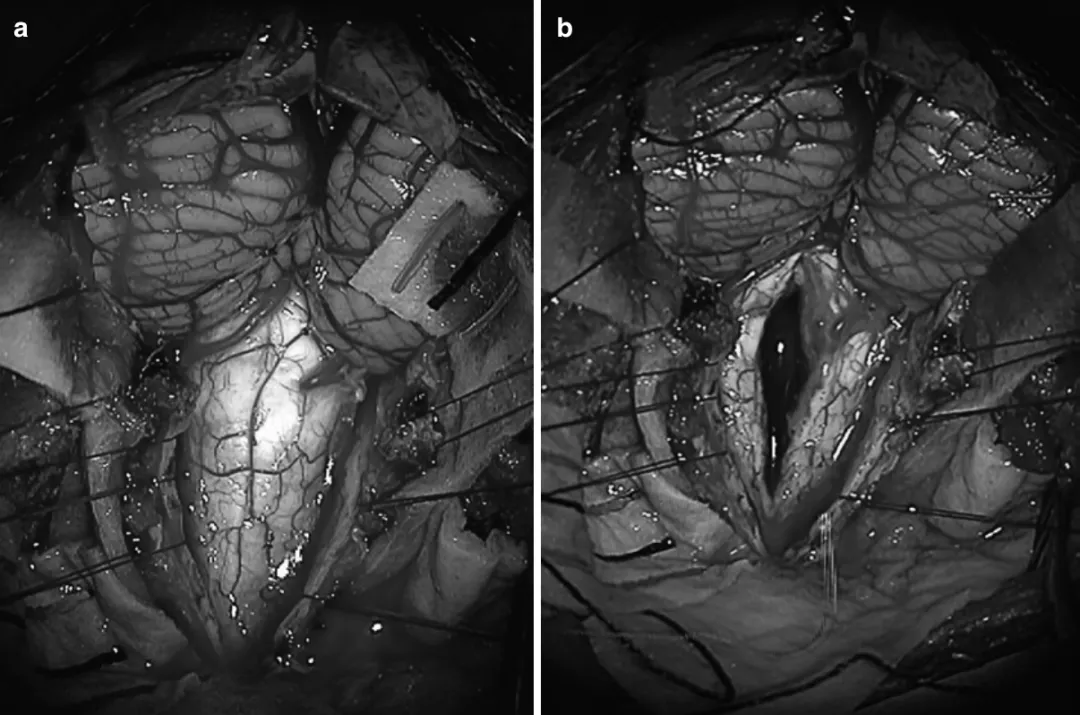

圖:延髓-頸髓膠質(zhì)瘤的術(shù)中照片圖,(a)后顱窩開顱后,可見延髓-頸髓膠質(zhì)瘤,在連續(xù)的術(shù)中神經(jīng)電生理(IONM)監(jiān)測(cè)下,使用CUSA超聲刀切除了腫瘤。(b)顯示腫瘤切除后的即時(shí)照片,顯示脊髓后正中線切開和延髓-頸髓膠質(zhì)瘤的切除。